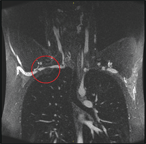

Primary extrahepatic bile duct neuroendocrine tumor with obstructive jaundice masquerading as a Klatskin tumor

Lauren Hoepfner and Jared A. White

Journal of Surgical Case Reports, Volume 2017, Issue 6, June 2017, rjx104, https://doi.org/10.1093/jscr/rjx104